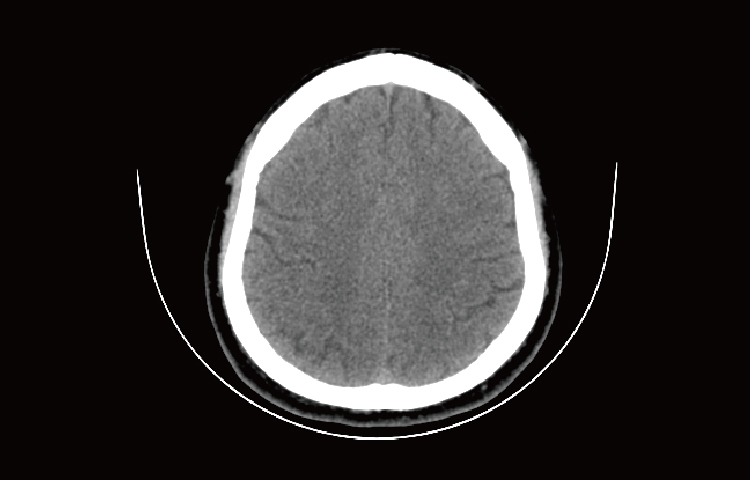

Скриншоты снимков